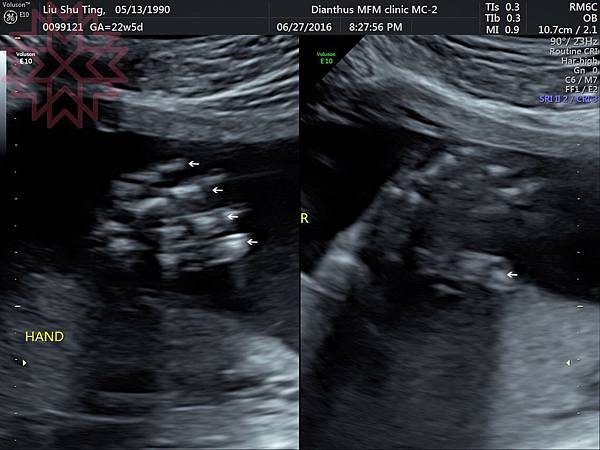

就是這樣哈哈哈哈哈哈哈哈(不得不說小手好可愛)

葉黃素的姿勢呈現一個跪臥,兩手手掌向外遮住自己臉的動作如下

好我知道超音波照很玄學看不懂,但是隱約可以看出葉黃素有三頭肌吧?哈哈哈史上最歪焦

最後分享幾張玄學超音波照~

這是兩邊的小手~~